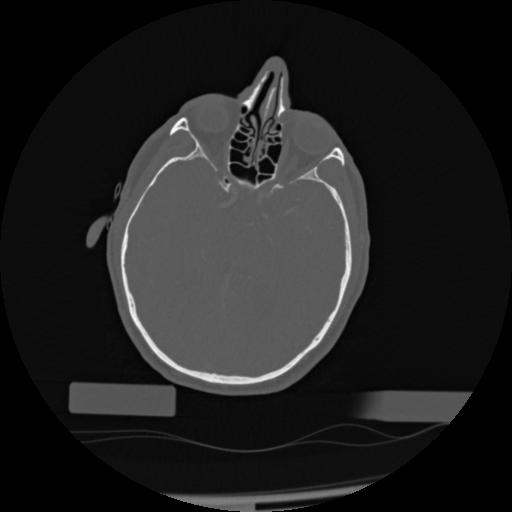

22 ANGIO,CE,Vol,0.5,ANGIO,,